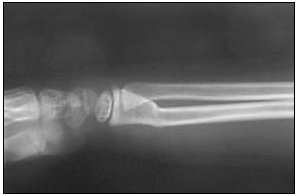

“Criança comparece ao atendimento após queda e apresenta a seguinte imagem radiográfica.”

A imagem anterior trata-se de uma fratura